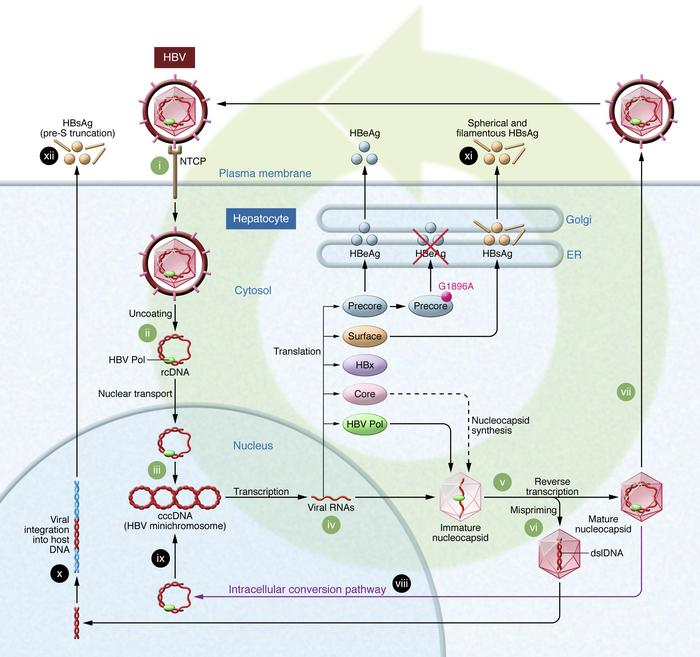

HBV

-

Hepadnarvirus (肝病毒科)

- enveloped

- DNA virus

- Icosahedral(二十面體) capsid

-

有反轉錄酶

- RNA-dependent DNA polymerase

- 把做出來的 mRNA 變回 dsDNA

-

可以插入宿主 DNA

-

mRNA

- 3.5 kb mRNA

- HBcAg:黏 DNA capsid

- HBeAg:會被分泌出來,可用於檢驗血液傳染性

- 2.1 kb mRNA

- S & M glycoproteins

- 2.4 kb mRNA

- L glycoprotein

- 3.5 kb mRNA

HBsAg: S, L, M

疾病公衛

-

Incubation period :45~120 天。

-

慢性肝炎 → 肝受損 → 肝纖維化(fibrosis) → 肝硬化(cirrhosis) → hepatocellular carcinoma (HCC,肝細胞癌)

-

1985 有疫苗

- recombinant vaccine

- Subunit vaccine (第一代)

- HBsAg

- S gene 的質體植入酵母 (第二代)

- 新生三劑

- 2~5 天、1 個月、6 個月

- 第一個疫苗預防的人類癌症

-

高傳染,20 億大盛行,3.5億慢性,其中65%中國,我們祖國真是太厲害了

- 亞洲剋星

- 健康成人89% 自己好,但孩童gg (30~90%慢性肝炎)

- Cell-mediated immunity (CTL) 很重要

- HBV 能夠在接觸到的表面存活約一週且仍具有 infectivity,如 table-tops、razor blades(剃刀片)、blood stains。

HBV 血液檢測

- 除了 HBcAg (黏在 capsid) 之外兩對半抗原抗體

- anti-HBs 才有保護作用

-

急性B肝

- Dane praticle: 完整構造

- Subviral praticle: 有抗原性空包彈

- window stage: HBsAg 驟降 → 測 anti-HBcAg

Subviral 很多(105),抓不到真的。

Subviral 可做疫苗(HBsAg)

- 慢性肝炎

- 產生 anti-HBe 才可能復原